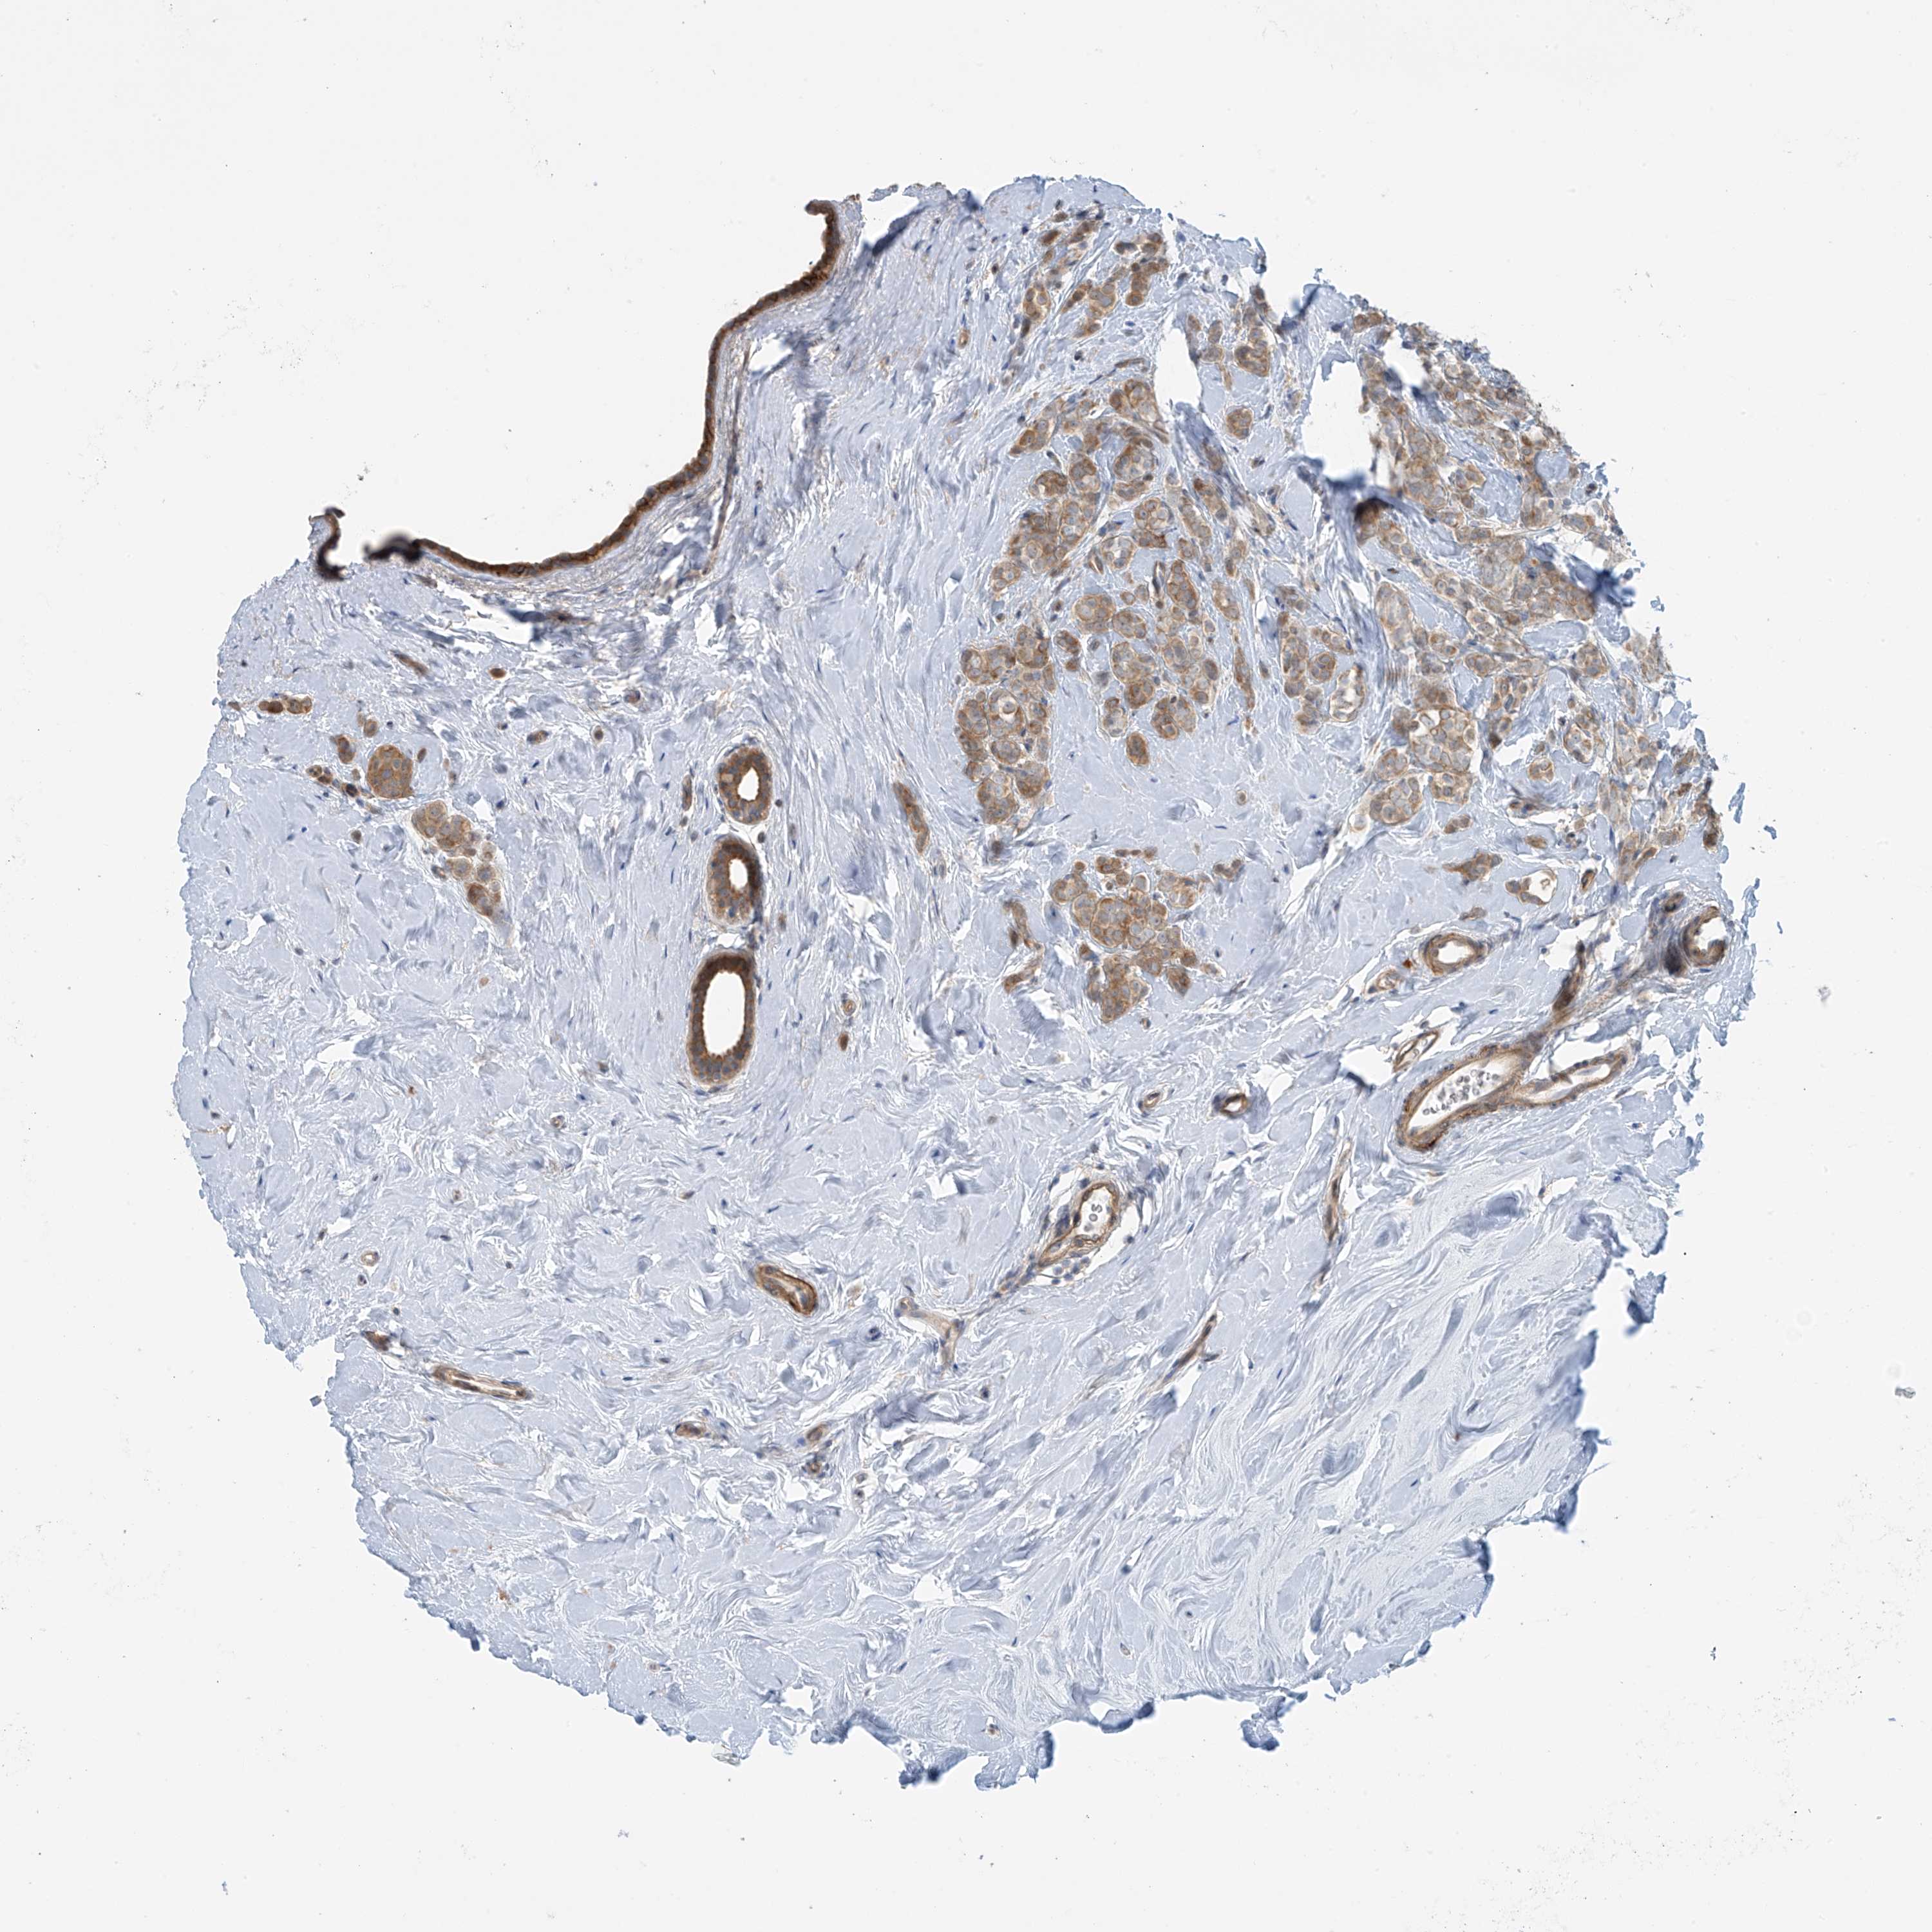

CANCER BREAST CANCER Show tissue menu

BRCA TCGA BRCA VALIDATION PROTEIN EXPRESSION